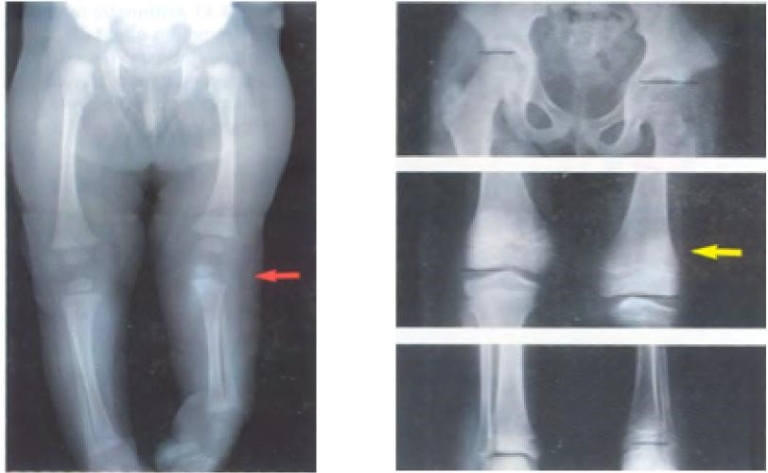

Examples of direct change in length are developmentally dislocated hips causing relative shortening of the lower extremity and fractures causing limb length inequality. Growth inhibition can be caused by numerous congenital diagnoses such as proximal femoral focal deficiency (PFFD) (Figure 1), fibular hemimelia, congenital short femur, posterior medial bowing, clubfoot or hemiatrophy. Other causes of growth inhibition include physeal injury from trauma, infection or irradiation as well as paralysis and tumors.

Growth stimulation occurs in congenital vascular malformations, vascular tumors, trauma and chronic inflammation (Figure 2).